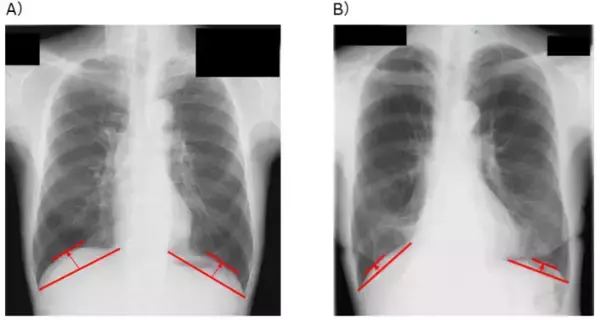

A)胸部X線画像による、横隔膜ドーム高の測定方法、B)横隔膜ドーム高が低い患者の例

そこで研究グループは、胸部X線画像から簡便に測定できる横隔膜の位置の高さである「横隔膜ドーム高※3」という指標に注目しました。横隔膜ドーム高は、肺機能や運動耐容能と密接に関連することが明らかになっており、より簡便かつ患者に負担なく術後予後を予測する指標となる可能性があります。しかし、これまで肺がん患者において、横隔膜ドーム高と術後の予後との関連性は明らかにされていませんでした。

術前1カ月以内に撮影された胸部X線画像から横隔膜ドーム高を測定し、術後の経過との関連を解析しました。

研究グループは、近畿大学病院において肺がんの肺葉切除術を受けた患者を対象に、術前1カ月以内に撮影された胸部X線画像を用い、肺腫瘍側の横隔膜ドーム高を測定しました。その結果、多変量解析※5 において、術前の横隔膜ドーム高は術後予後に影響を及ぼすことが知られている喫煙状況、肺機能、がんのステージなどの因子の影響を受けず、独立した術後予後を予測できる因子であることが明らかとなりました(HR=2.10、p

※3 横隔膜ドーム高:横隔膜がどれくらい上に持ち上がっているか(高さ)を示す指標。